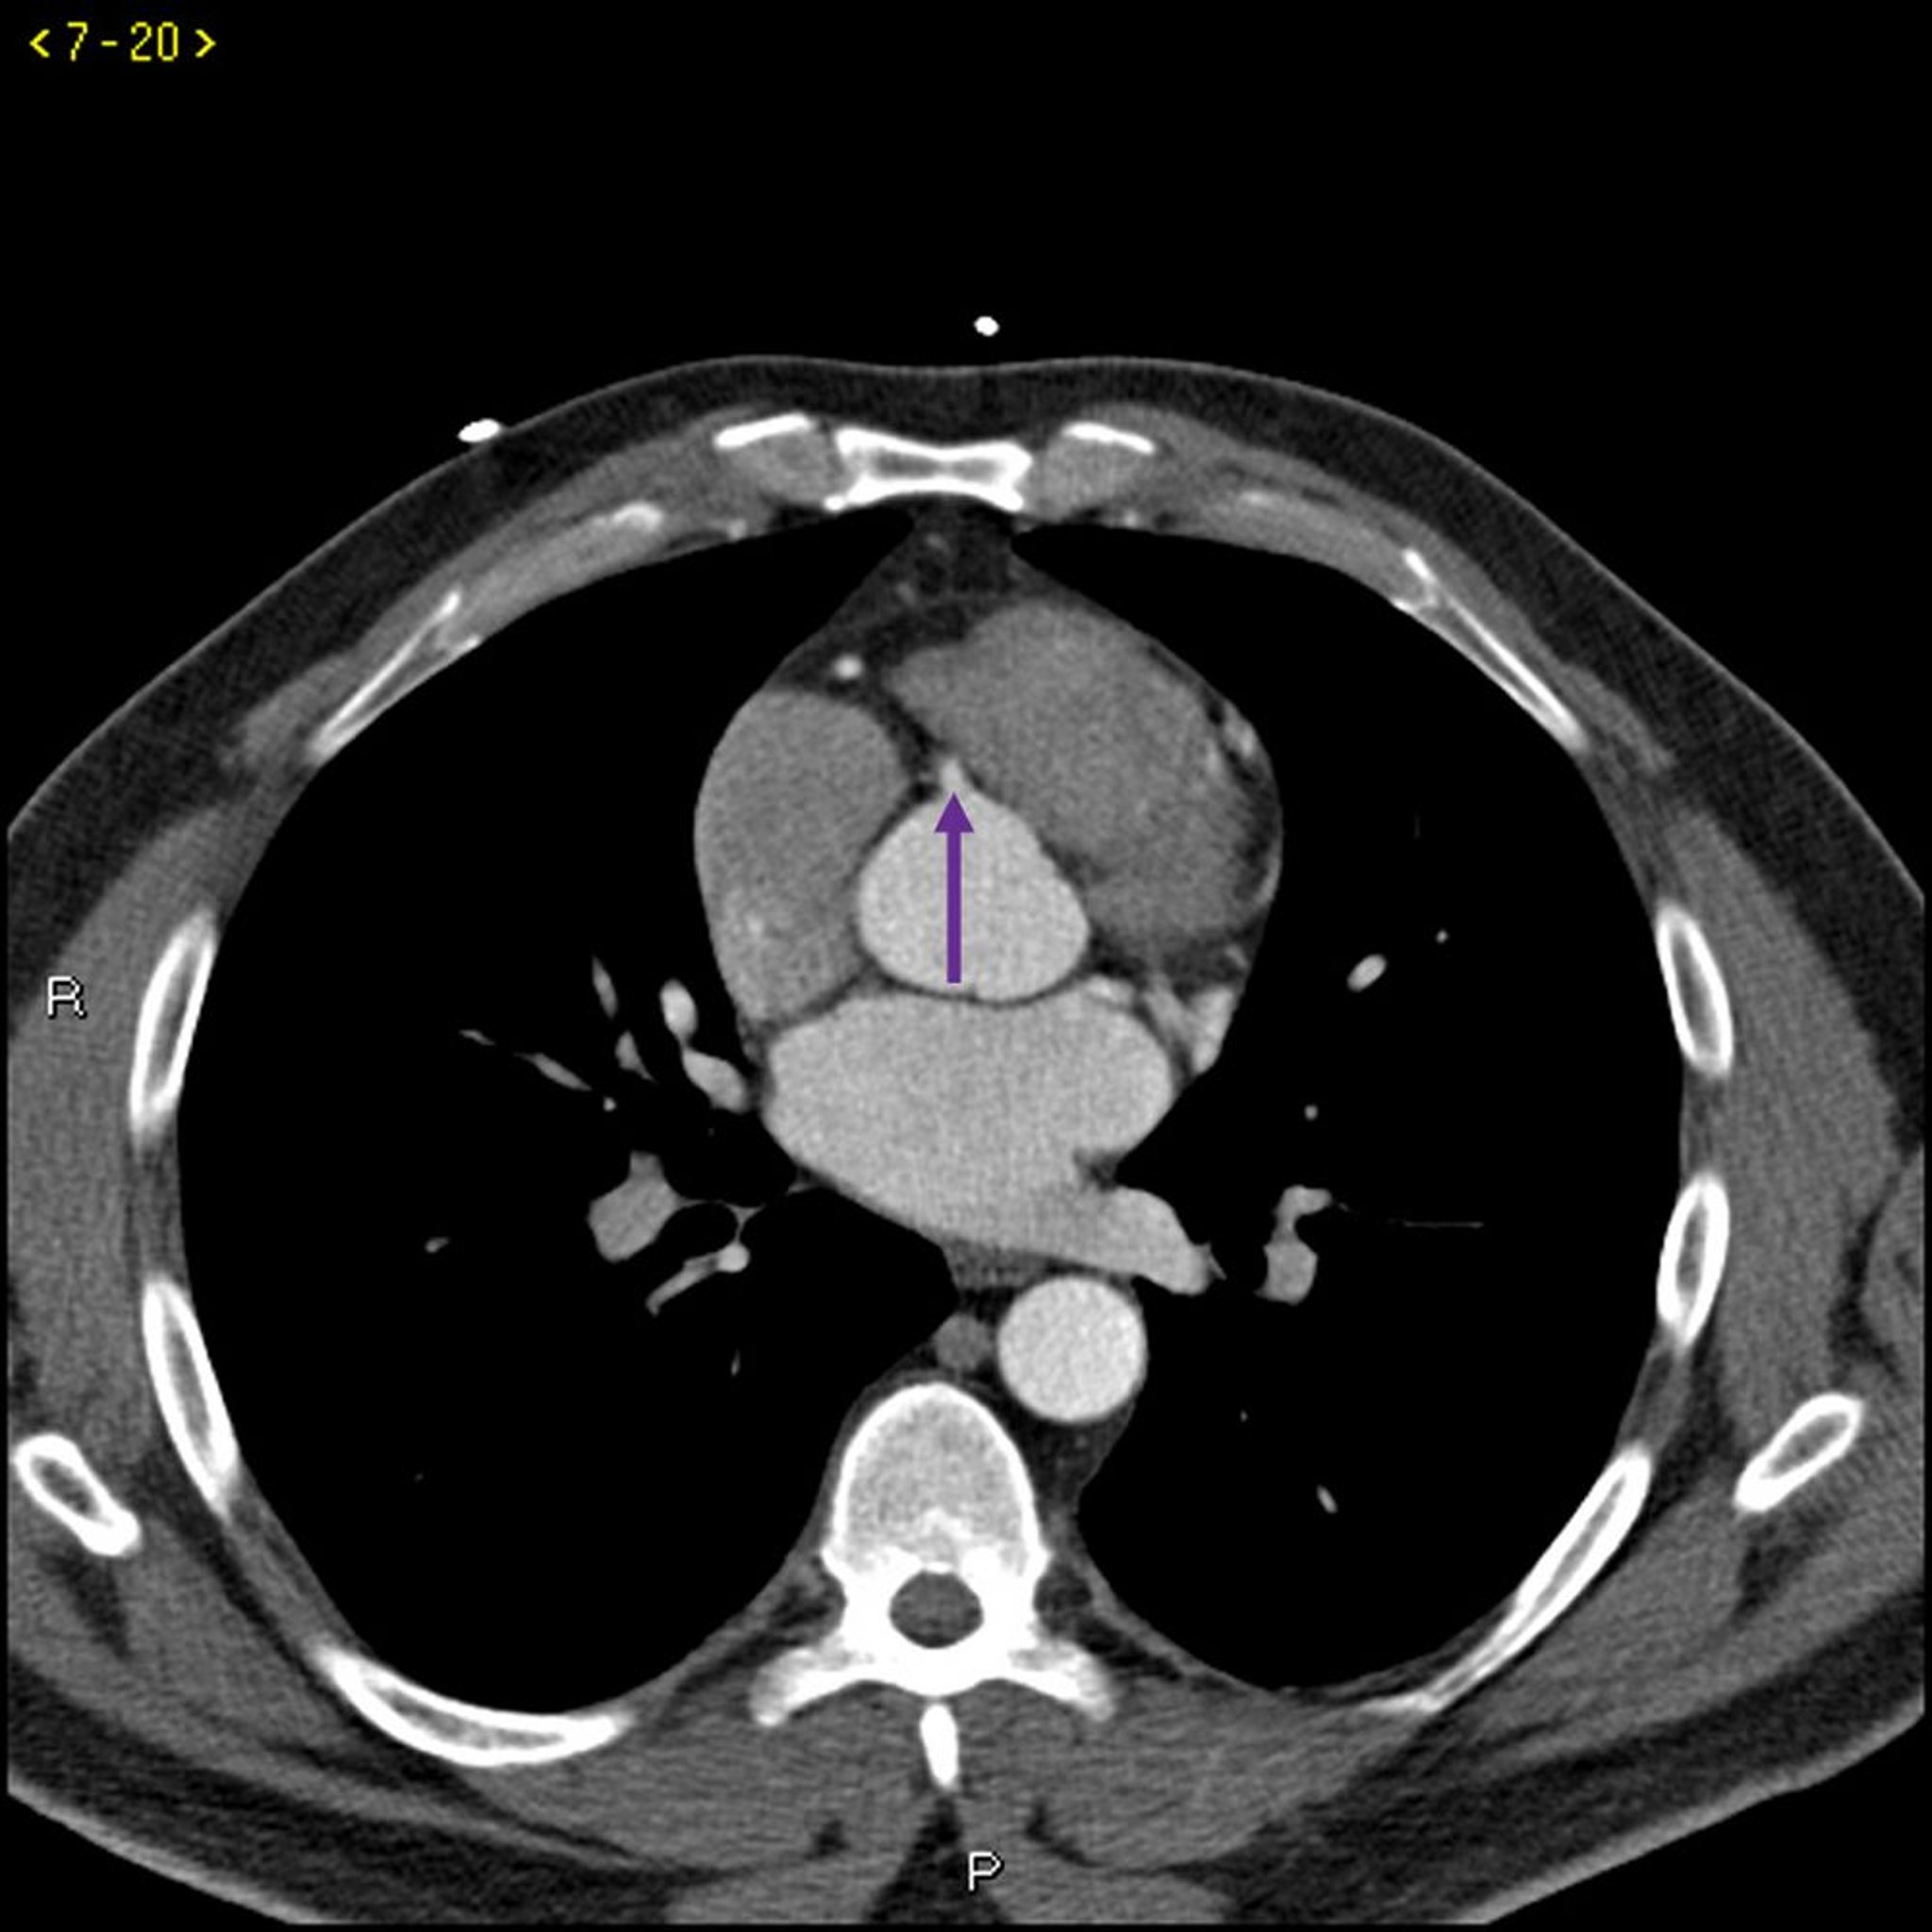

TDM avec contraste montrant des artères coronaires normales – Coupe 5

Cette TDM avec contraste montre des artères coronaires normales. Le tronc commun coronaire gauche est indiqué par la flèche rouge. Les artères interventriculaire antérieure gauche et circonflexe gauche sont indiquées par les flèches verte et bleue respectivement et l'artère coronaire droite est indiquée par la flèche violette.